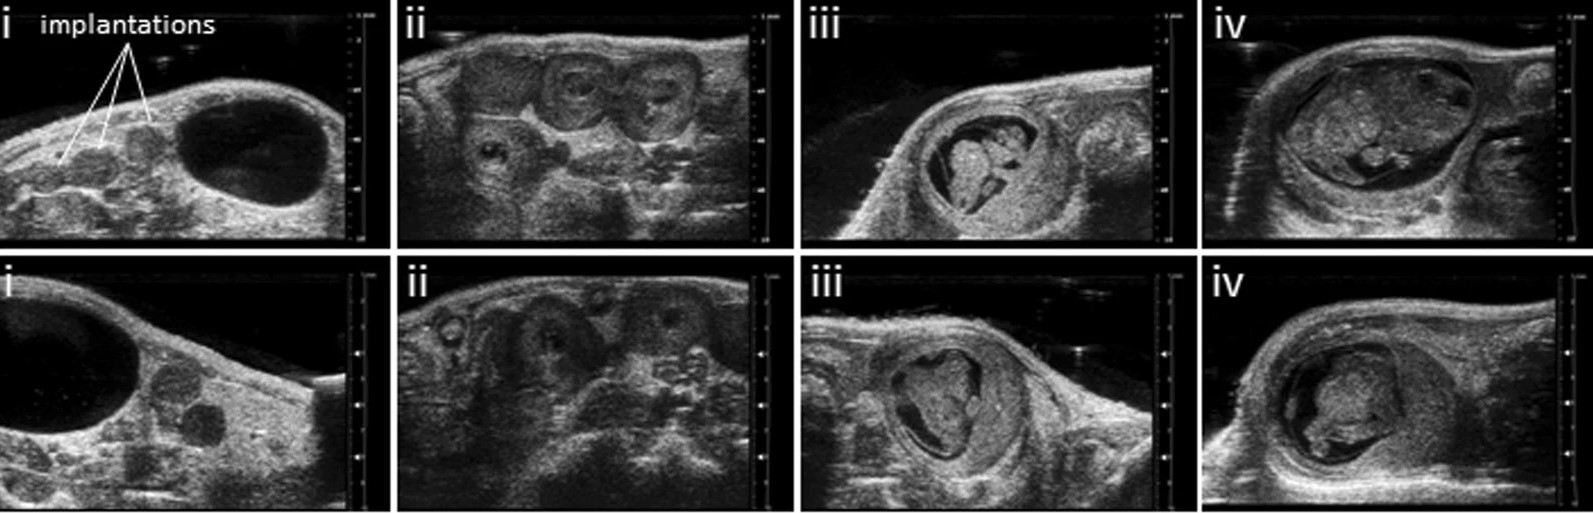

Reprod. Sci. 31 (1 Suppl.), 332A - 332A 10.1007/s43032-024-01501-2 Zenclussen, M.L., Ulrich, S., Bauer, M. , Fink, B. , Zenclussen, A.C. , Schumacher, A. , Meyer, N. (2024):

Absence of heme oxygenase-1 affects trophoblastic spheroid implantation and provokes dysregulation of stress and angiogenesis gene expression in the uterus